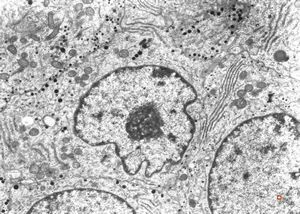

M, 38y. | pheochromocytoma